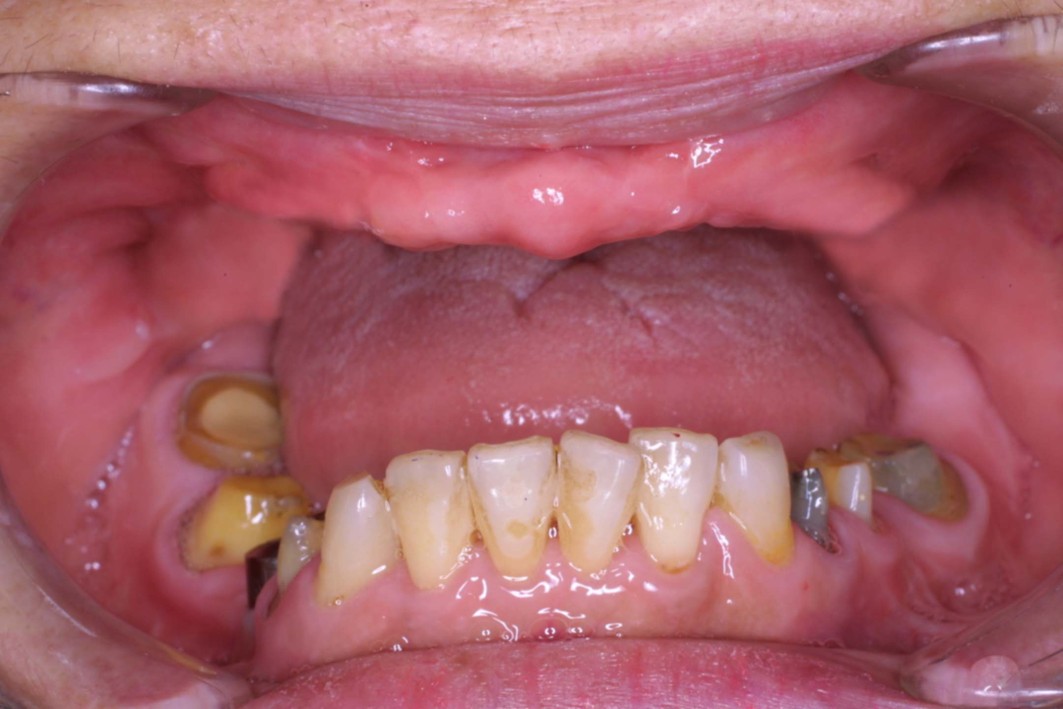

歯がボロボロの状態になってしまった患者さんには、それぞれに至った背景や理由があります。虫歯や歯周病になりやすい体質の方もいらっしゃいますが、多くの場合、過去の治療で感じた強い痛みや歯科医院でのつらい経験がトラウマとなり、歯科医院そのものが苦手になってしまったケースがほとんどです。その結果、治療を後回しにせざるを得なかった方も少なくありません。

だからこそ、今悩んでいる患者さんにお伝えしたいことがあります。たとえ歯がボロボロの状態であっても、適切な歯科治療を受けることで、美しく機能的な歯を取り戻すことは十分に可能です。